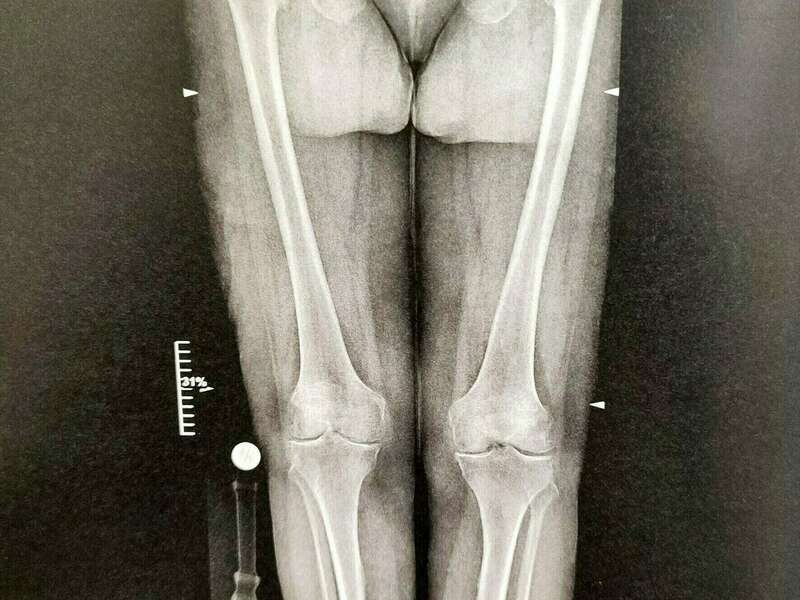

L’arthrose est un véritable problème de santé publique de nos jours. Elle représente l’une des principales causes de perte d’autonomie chez les personnes âgées. On estime qu’environ 65% des sujets de plus de 65 ans souffrirait d’arthrose. La gonarthrose concerne 30% des personnes de 65 à 75 ans. L’atteinte fémoro-tibiale interne est la plus fréquente et peut être due à une déviation de l’axe mécanique. L’atteinte fémoro-patellaire concerne plus souvent les sujets jeunes faisant suite à un traumatisme endommageant le cartilage ou à une instabilité de la rotule.

- Les déformations d’axe : genu varum (jambes arquées) et genu valgum (jambe en X)

Elle sera confirmée par des examens radiologiques tels que des radiographies du genou. En cas de doute diagnostic ou afin de rechercher d’éventuelles lésions associées, un scanner et/ou une IRM pourront être prescrits.